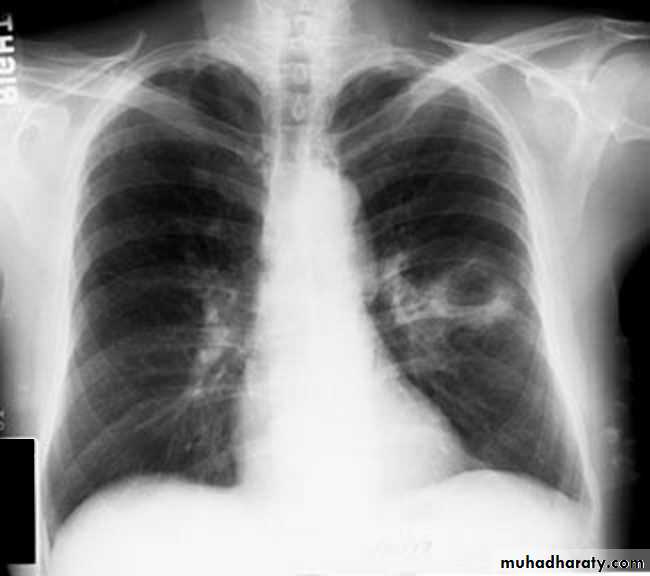

Nodular (coin) lesion in the left upper lung with irregular edge (most probably cancinoma